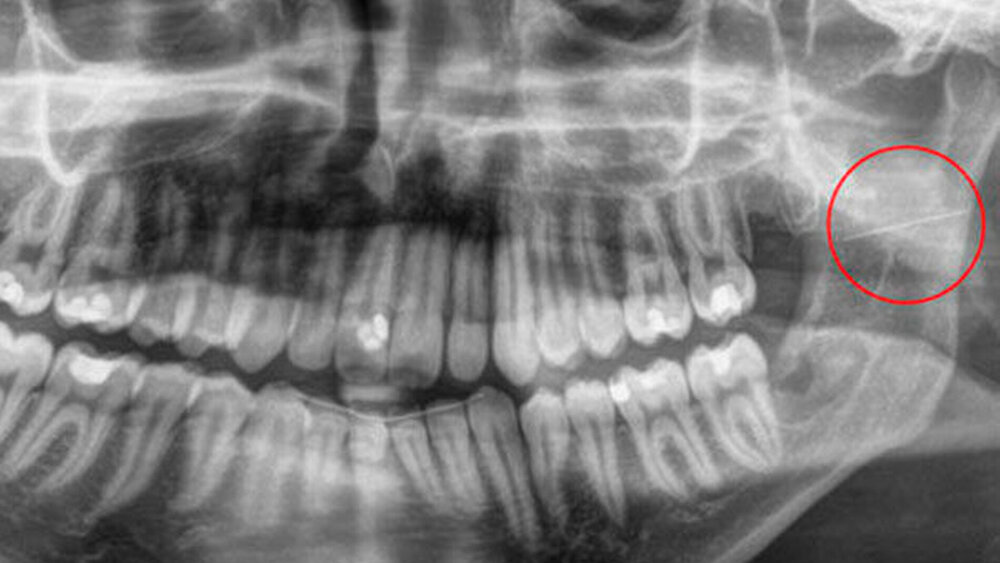

Wir berichten über den Fall eines 29-jährigen Patienten, welcher notfallmäßig vom niedergelassenen MKG-Chirurgen nach einer Weisheitszahn-Osteotomie regio 28 und 38 in unsere Klinik überwiesen wurde. Im Rahmen des ambulanten Eingriffs in lokaler Anästhesie wurde eine Leitungsanästhesie im Bereich des Nervus (N.) alveolaris inferior links vorgenommen. Nach erfolgreicher Osteotomie des linken unteren Weisheitszahns imponierte in der postoperativen Röntgenkontrolle (Orthopantomogramm) ein circa 2,5 cm langer metallischer Fremdkörper im Bereich des aufsteigenden Unterkieferastes links (Abbildung 1).

Hier zeigte sich als Corpus alienum die frakturierte Kanüle in unveränderter Position im Bereich der medialen Seite des aufsteigenden Unterkieferastes auf Höhe des Foramen mandibulae zwischen Unterkieferknochen und Musculus pterygoideus medialis (Abbildungen 2, 3).